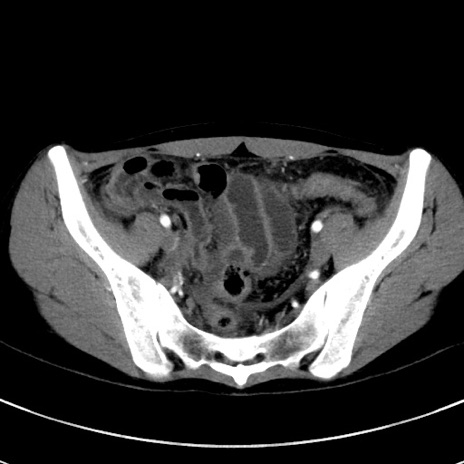

症例17(横断像)

【症例】20歳代女性

【主訴】嘔吐、下腹部痛

【現病歴】昨日夕食後に嘔吐し下腹部痛が出現。本日になっても嘔吐持続し改善しないため来院。

【身体所見】意識清明、BT 37.2℃、BP 108/67mmHg、腹部:平坦、やや硬、下腹部正中から右にかけて圧痛あり、反跳痛軽度あり、tapping pain(+)。

【データ】WBC 13600、CRP 14.94